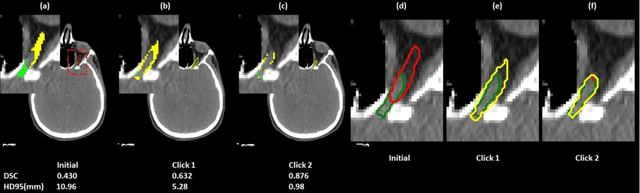

Abstract:Automatic segmentation of anatomical structures is critical for many medical applications. However, the results are not always clinically acceptable and require tedious manual revision. Here, we present a novel concept called artificial intelligence assisted contour revision (AIACR) and demonstrate its feasibility. The proposed clinical workflow of AIACR is as follows given an initial contour that requires a clinicians revision, the clinician indicates where a large revision is needed, and a trained deep learning (DL) model takes this input to update the contour. This process repeats until a clinically acceptable contour is achieved. The DL model is designed to minimize the clinicians input at each iteration and to minimize the number of iterations needed to reach acceptance. In this proof-of-concept study, we demonstrated the concept on 2D axial images of three head-and-neck cancer datasets, with the clinicians input at each iteration being one mouse click on the desired location of the contour segment. The performance of the model is quantified with Dice Similarity Coefficient (DSC) and 95th percentile of Hausdorff Distance (HD95). The average DSC/HD95 (mm) of the auto-generated initial contours were 0.82/4.3, 0.73/5.6 and 0.67/11.4 for three datasets, which were improved to 0.91/2.1, 0.86/2.4 and 0.86/4.7 with three mouse clicks, respectively. Each DL-based contour update requires around 20 ms. We proposed a novel AIACR concept that uses DL models to assist clinicians in revising contours in an efficient and effective way, and we demonstrated its feasibility by using 2D axial CT images from three head-and-neck cancer datasets.